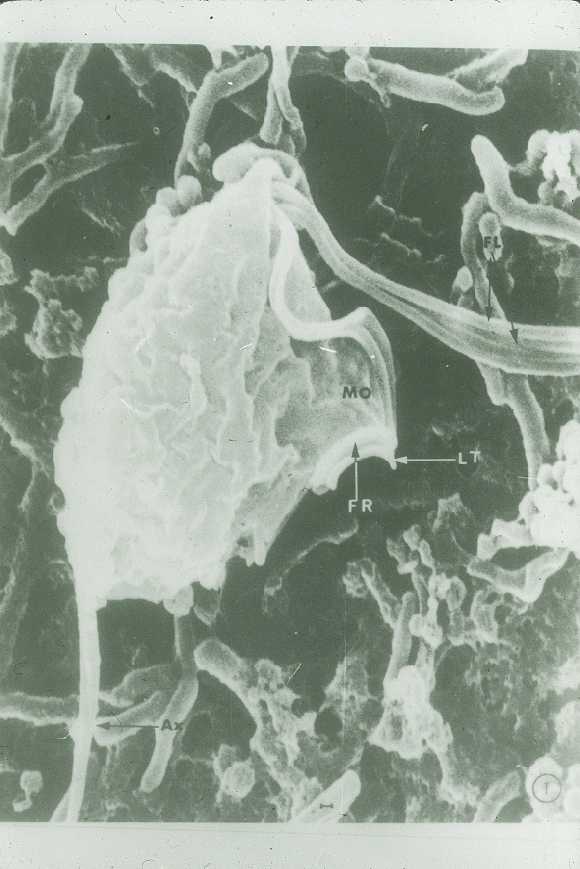

Diente tratado durante su desarrollo con LiCl. En este experimento se realizó un cultivo organotípico de primeros molares extraídos a los 14 días de desarrollo embrionario. A este cultivo se le añadió LiCl a baja concentración, de modo que se sobreactivó la vía de señalización Wnt. Una vez crecido así el diente durante una semana in vitro se introdujo dentro del testículo de un ratón adulto, donde permaneció hasta el final de su desarrollo. Pasadas 3 semanas se extrajo el testículo y con él las piezas dentales que se habían desarrollado. La que se observa en esta imagen es una de estas piezas la cual presenta un fenotipo altamente modificado debido al tratamiento al que se ha visto sometido durante su desarrollo. La sábana de lino que parece envolver al diente Faraón en su descanso final, son los restos de tejido periodontal.

Fragmento de diente de ratón adulto.

La presente imagen muestra un fragmento de un diente de ratón adulto, el cual se ha extraído, limpiado y procesado para microscopía electrónica de barrido. La pieza dental, a priori lisa y firme, se encuentra constituida por millones de fibras que se entrelazan hasta formar un tejido duro y resistente. Son varias las capas que conforman un diente; entre ellas, el esmalte y la dentina destacan, no sólo, por su importancia fisiológica sino también por su maravillosa morfología. La dentina, formada por unas células llamadas odontoblastos, aparece, necesariamente, antes que el esmalte, e induce la formación del mismo. Esta capa aporta, a la vez, dureza y flexibilidad, debido a su composición heterogénea entre cristales de hidroxiapatita y fibras colágenas.

Sobre ella se encuentra el esmalte, formado por un mar de cristales de hidroxiapatita que le confieren su dureza e insensibilidad ante diversos estímulos. Esta capa, prácticamente transparente, y que adquiere su color de la dentina, ostenta el puesto del tejido más duro de todo el cuerpo.

Molar de ratón.

Este molar de ratón, observado mediante microscopia electrónica de barrido ha recorrido un complejo camino hasta su total desarrollo, apreciable en esta imagen. El germen dental de 14 días de desarrollo embrionario, tras ser cultivado in vitro en presencia de LiCl (activador de la ruta Wnt) y trasplantado a testículos de ratones receptores, muestra un extraño fenotipo, a todas luces modificado por el tratamiento soportado. Resulta apreciable en la imagen la presencia de múltiples crestas dentales de un tamaño reducido, así como una corona aplanada que hace parecer a este diente una pila bautismal.